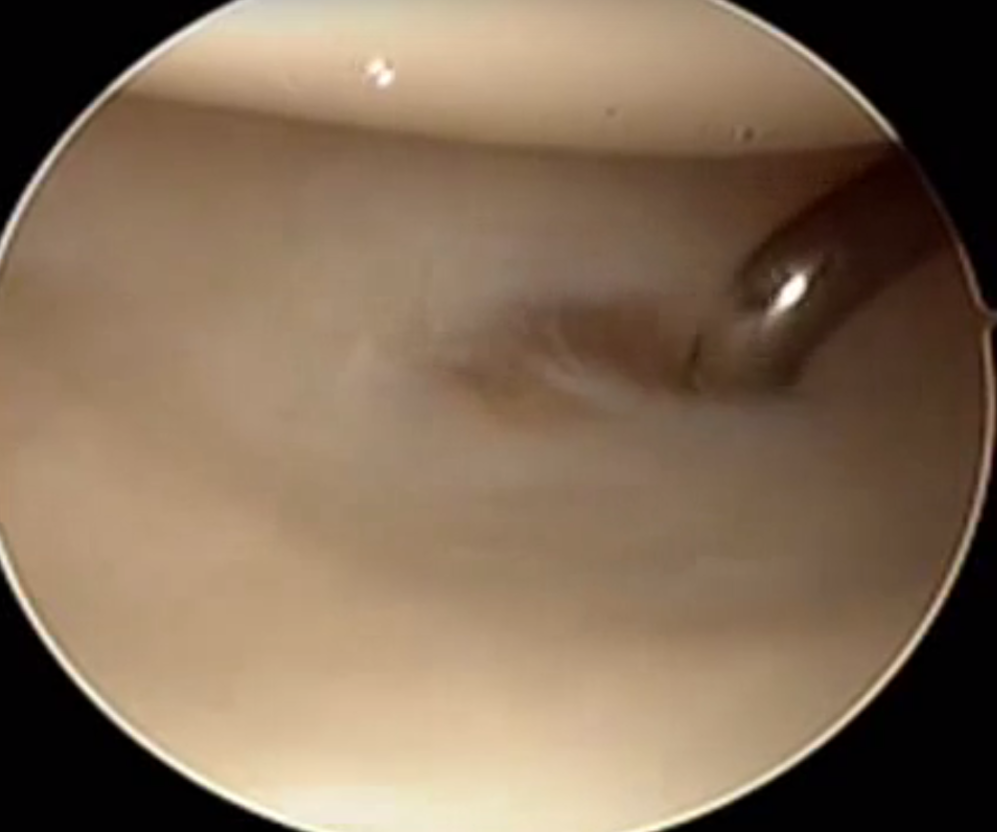

Ulna / foveal sided TFCC tear on arthroscopy

Technique

- viewing via 3-4 portal

- instrumentation via 6R +/- 6U portal (either side of ECU)

- pass outside in and suture over capsule

- suture anchor repair

- drill hole in ulna